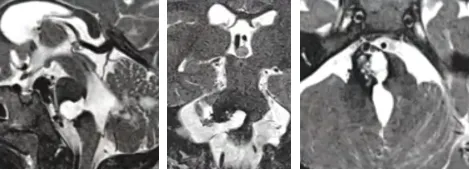

脑干海绵状血管瘤二次出血

直到这时我才明白,为什么妈妈爸爸会如此紧张我,原来1年前的那场手术并没有将我的脑干海绵状血管瘤切干净,一部分剩余的血管瘤再次引发了脑干出血,逐渐让我变得奇怪……